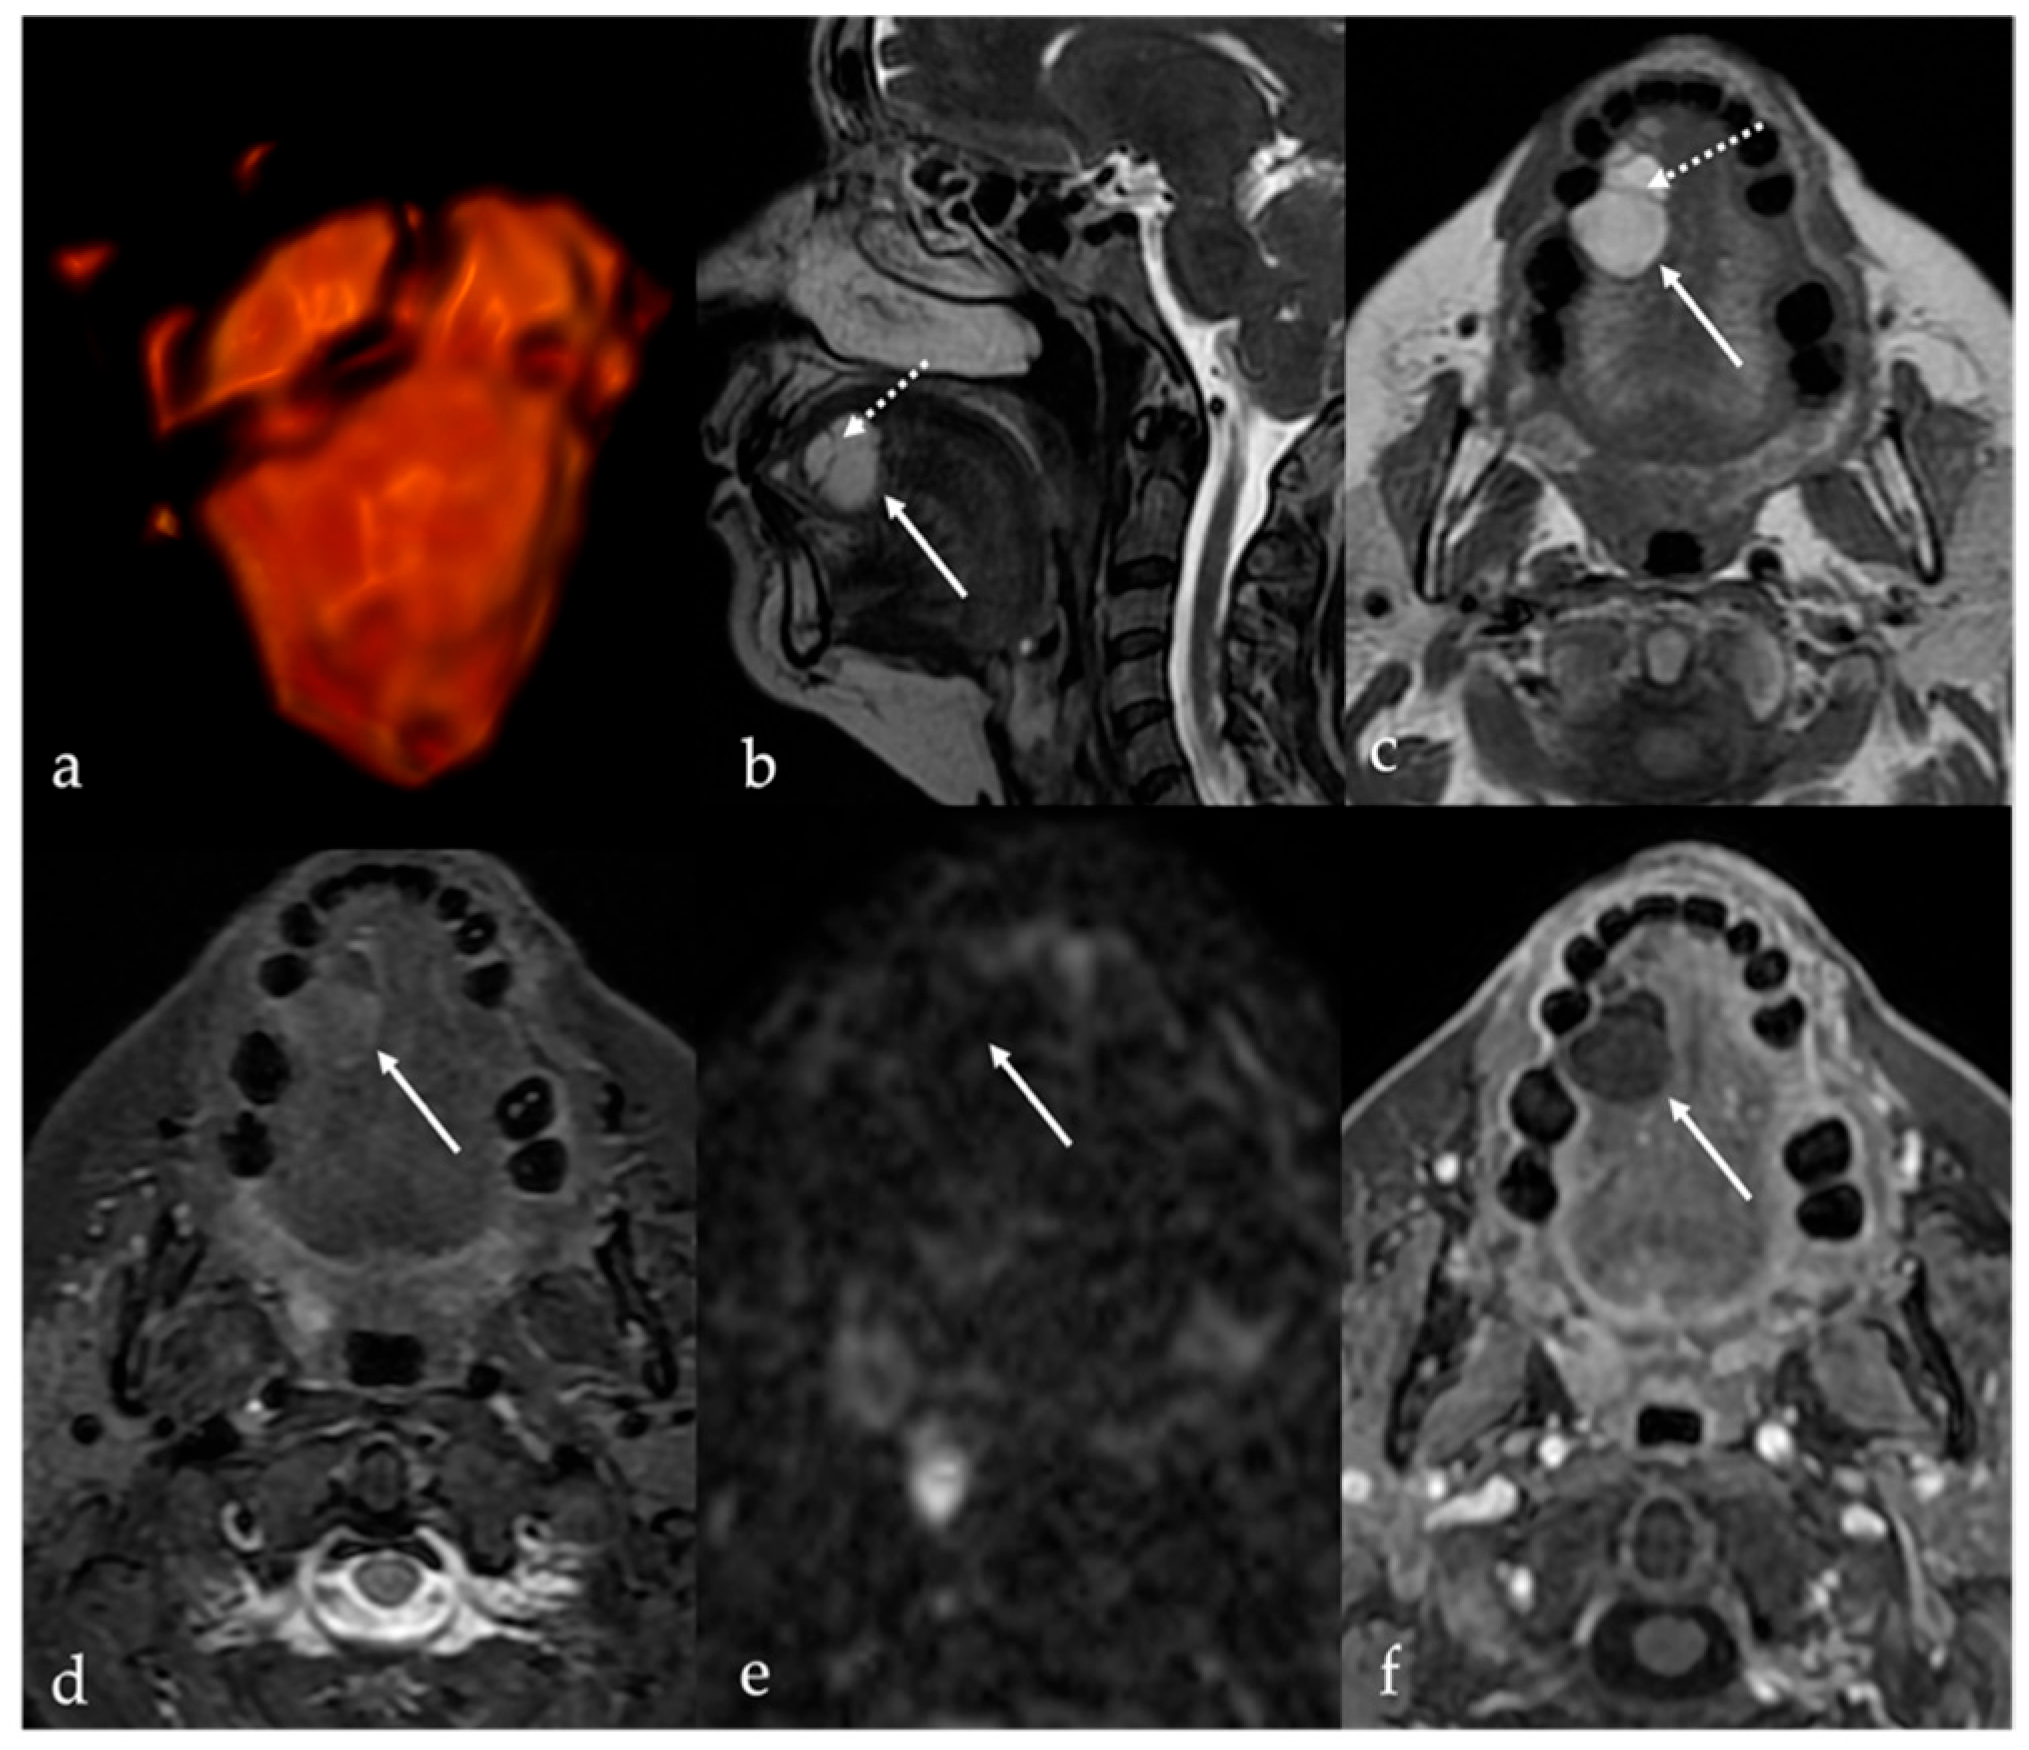

7.1. Thyroglossal Duct Cyst

| Thyroglossal duct cyst [15] Ectopic thyroid tissue [16] | Cyst Same features as thyroid tissue | Lingual tonsil mucous retention cyst Squamous cell carcinoma and lymphoma of the tongue base |